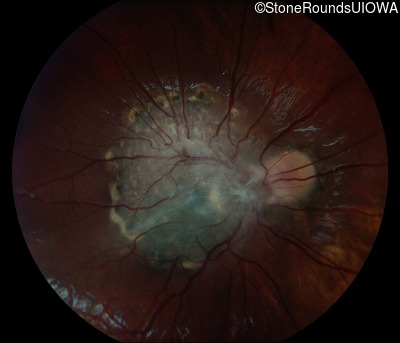

This 9 year old male was noted to have some crossing of his eyes at 2 months of age and the eye exam which followed identified a retinal lesion in the right eye. When he was six years old an epiretinal membrane was noted in his left eye. Two years later it was decided that it was a thin hamartoma in that eye as well. He underwent neuroimaging at age 7 which identified bilateral acoustic neuromas.

| Age at visit: 7 years |

| Age at visit: 10 years |

| Age at visit: 11 years |

| Age at visit: 14 years |